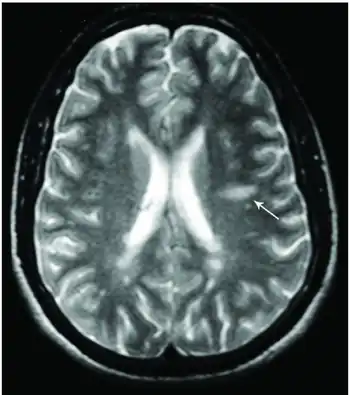

This morphologic appearance was named Dawson's fingers by Charles Lumsden, after the Scottish pathologist James Walker Dawson,[31] who first defined the condition in 1916.

Dawson's fingers

Image shows multiple lesions in periventricular and subcortical white matter, Dawson's finger is a characteristic finding in multiple sclerosis

"Dawson's fingers" is the name for the lesions around the ventricle-based brain veins[32][33] of patients with multiple sclerosis and antiMOG associated encephalomyelitis[34]

Though once thought to be specific of MS, it is known not to be the case.[35]

The condition is thought to be the result of inflammation or mechanical damage by blood pressure[30] around long axis of medular veins.

Dawson's fingers spread along, and from, large periventricular collecting veins, and are attributed to perivenular inflammation.[36]

Lesions far away from these veins are known as Steiner's splashes.[30]